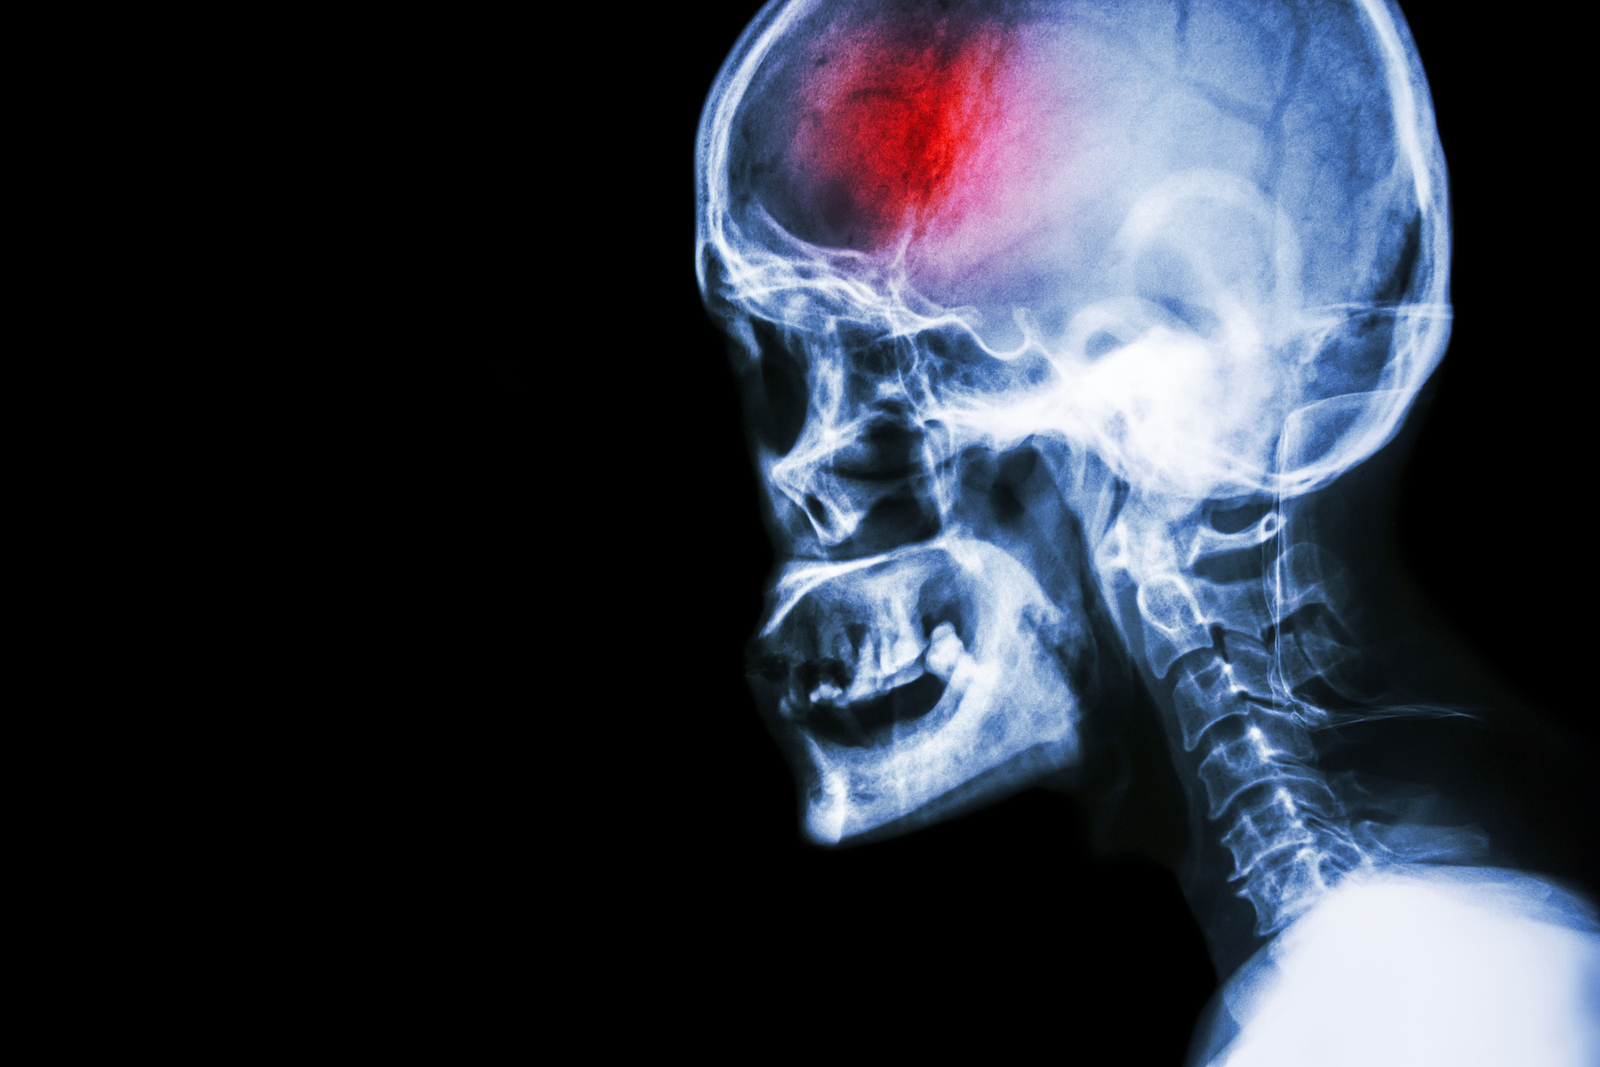

What is a stroke?

A stroke (previously known as a cerebrovascular accident) when there is a decreased flow of blood to the brain from either a blockage in the blood vessels that supply the brain (ischemic stroke), or a bleed from the blood vessels that supply the brain (hemorrhagic stroke). When the blood flow to the brain is blocked it prevents the brain from getting the needed oxygen and nutrients to function. Without oxygen the brain cells can be permanently damaged or die and the physical and mental functions related to that area of the brain will be affected. A stroke is a medical emergency and rapid treatment is crucial to decreasing the damage caused by a stroke.

Types of strokes

There are three types of strokes:

- Ischemic stroke: a stroke that is caused by a blockage (clot) that disturbs the blood flow to the brain.

- Hemorrhagic stroke: a stroke that is caused by a bleed that disturbs the blood flow to the brain and puts pressure on the surrounding tissue.

- Transient ischemic attack: often referred to as a “mini-stroke” or TIA, where the blood flow to the brain is temporarily disturbed and as a result causes temporary signs and symptoms of a stroke that resolve quickly .

Diagnosis

The classic signs and symptoms of a stroke often create an obvious suspicion of stroke, however once at a medical centre, other objective tests are completed to confirm the stroke diagnosis. It is important for the medical team to determine which kind of stroke is occurring in order to assist with the most effective type of treatment.

Computed Tomography (CT) scan and/or Magnetic Resonance Imaging (MRI) scan: These tests are done on your brain and used to locate the exact location of the stroke and to determine if it has been caused by a blockage or a bleed. These tests can also help rule out other conditions that may be causing symptoms, such as an infection or a brain tumour